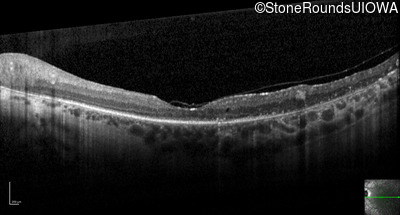

Optical Coherence Tomography - Right - 20/40 +1

Exemplar / OCT Stack